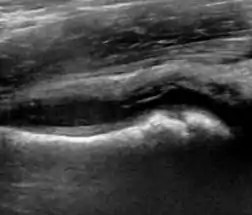

During childhood, ultrasound is a quick method to assess hip pain and quite often may be used to avoid use of irradiating techniques, such as radiography or CT. Ultrasound allows evaluation of joint effusion, synovial thickening and neovascularity, the bone/cartilage contour, and the femoral head-neck alignment. Although sonography is extremely sensitive in detecting increased synovial fluid, it is nonspecific and cannot be used with accuracy to determine the type of fluid. Transient synovitis of the hip, despite being the most frequent cause of pain in children between 3 and 10 years, remains a diagnosis of exclusion. It usually shows anechoic fluid, but echogenic fluid can also be found. The effusion is considered pathologic when it is measured at >2 mm in thickness. The differential diagnosis is wide, including osteomyelitis, septic arthritis, primary or metastatic lesions, LCPD, and SCFE. Discrimination from septic arthritis is challenging, often requiring joint aspiration. In septic arthritis, US is able to demonstrate a hip joint effusion, synovial thickening, and cartilage damage, although the appearances are nonspecific.[1]

Figure 12:

Normal ultrasound appearance of the femoral head-neck junction.

Joint effusion in transient synovitis of the hip.